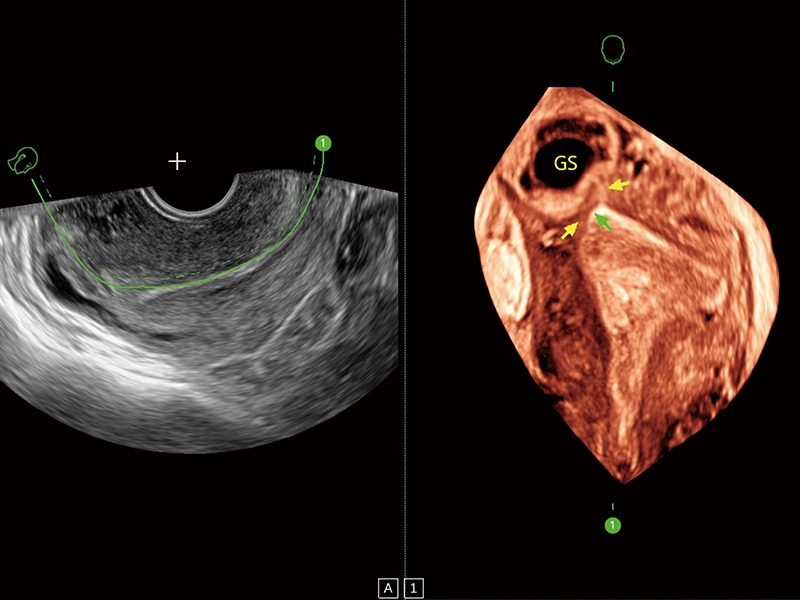

临床图

超声引导下双侧卵巢穿刺取卵

卵巢多囊样改变